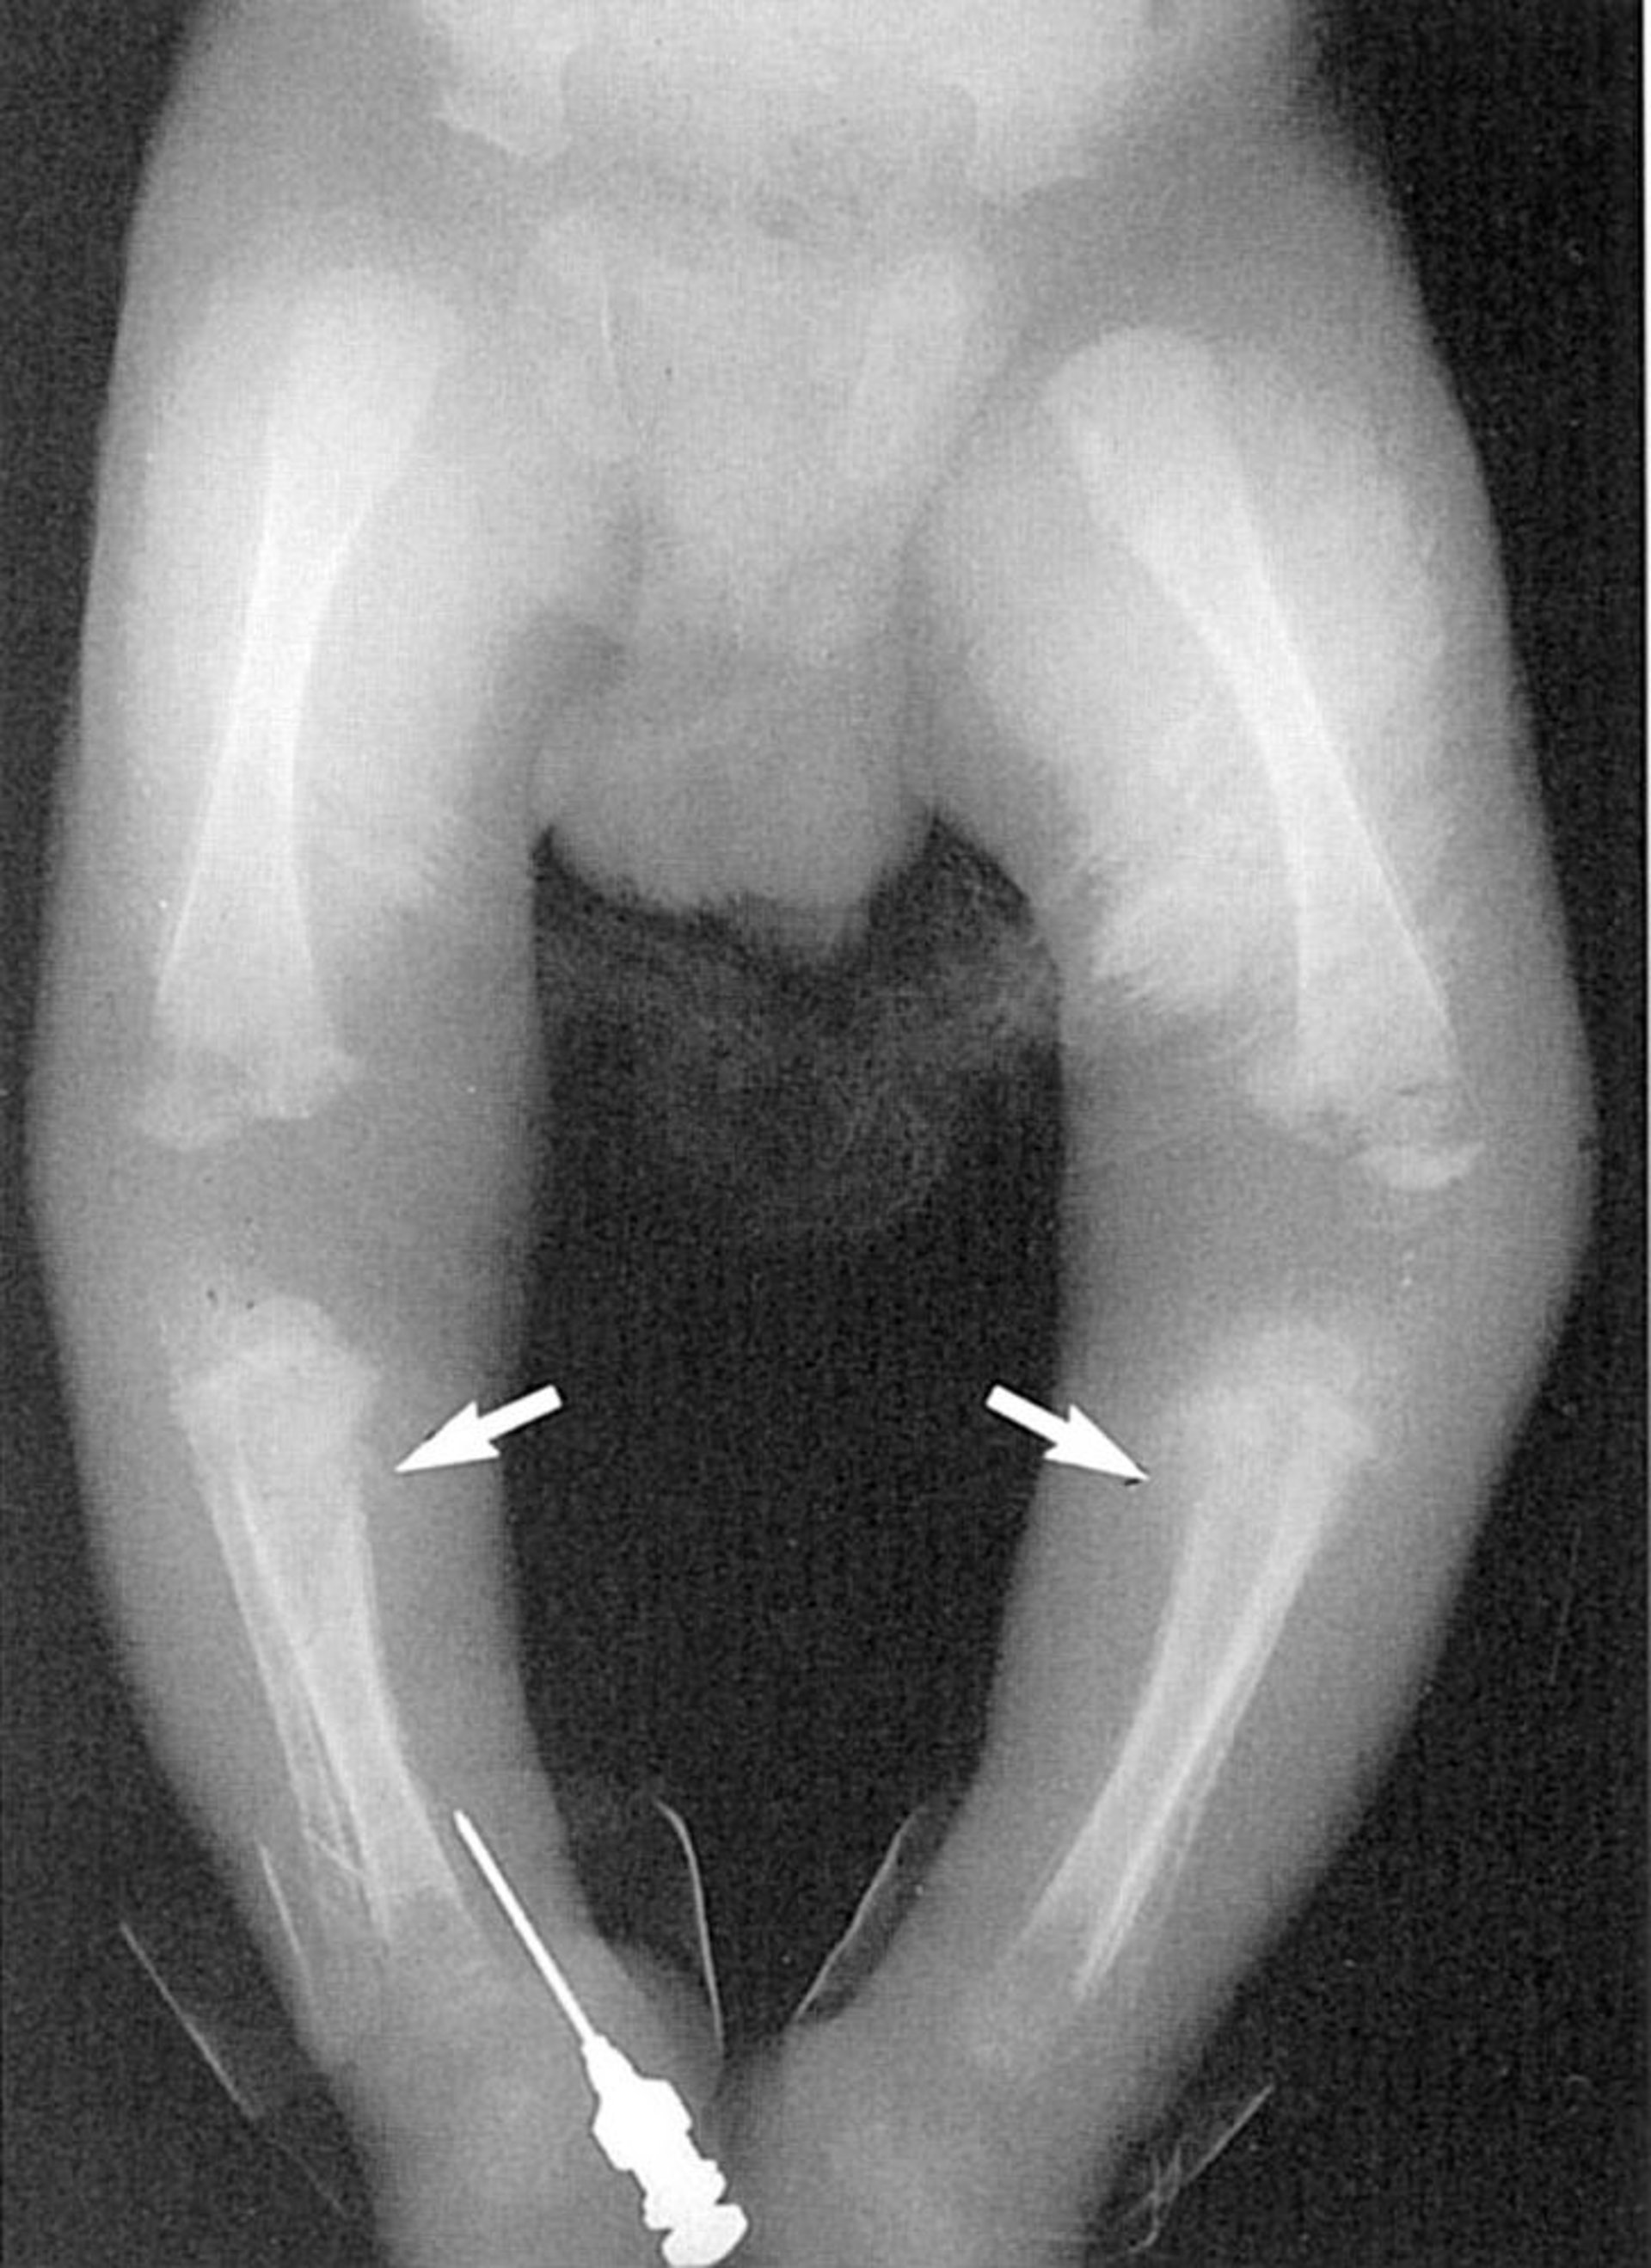

Sinal de Wimberger

Esta foto mostra lesões líticas na região medial da tíbia proximal (flechas).